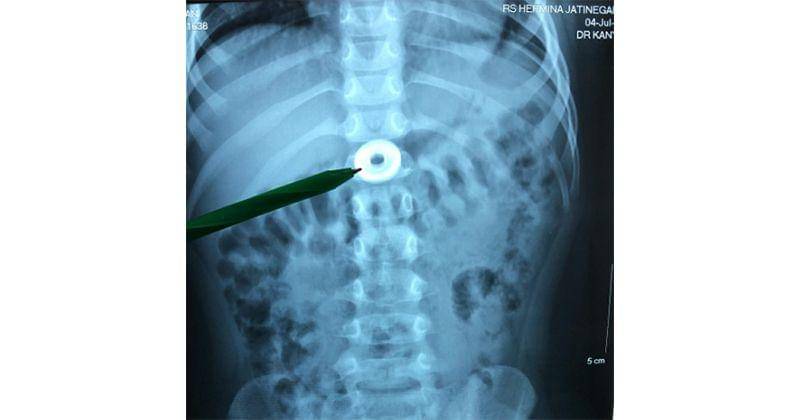

1. Kasus lainnya, anak menelan kancing selama 10 hari

Seorang pasien berusia 4 tahun dilaporkan menelan kancing. Benda asing tersebut diketahui menyelinap di dalam tubuh pasien karena terlihat jelas dari hasil ronsen.

Menurut dr. Kanya, anak tersebut sedang melempar-lempar kancing celana jins ke atas kemudian kancing tersebut masuk ke dalam mulutnya dan tertelan. Sungguh sederhana ketika Si Kecil melewati kejadian seperti itu, dalam waktu sekejap mereka tidak menyadari ada sesuatu yang berubah dengan kesehatan tubuhnya.

Pada kasus anak menelan kancing, karena ukuran kancing tidak terlalu kecil maka tidak keluar lewat "pintu" belakang lambung yang menuju usus, menurut penjelasan dr. Kanya.

Solusinya adalah dengan melakukan EGD atau endoskopi dengan selang berujung khusus serupa capitan. Nantinya alat tersebut masuk ke lambung dan berusaha mencapit dan menarik kancing keluar dari tubuh pasien.

Ada risiko yang besar ketika proses itu dilakukan, salah satunya adalah pada saat proses menarik kancing keluar dan benda asing tersebut kembali terjatuh kemudian menutup saluran napas. Maka akibatnya bisa sangat fatal.